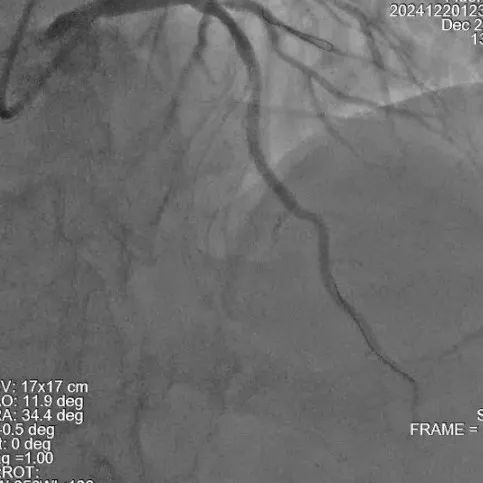

冠脉造影

手术过程

尹秋林主任表示本次手术很顺利。该患者左冠和右冠病变均较为局限,且患者及家属对植入生物可吸收支架意向强烈。在腔内影像IVUS的引导下评估管腔尺寸,病变性质后做精准预处理。本次手术中FIRESORB®具有较好的推送性,径向支撑表现也很好。我们会持续关注患者术后的恢复情况。